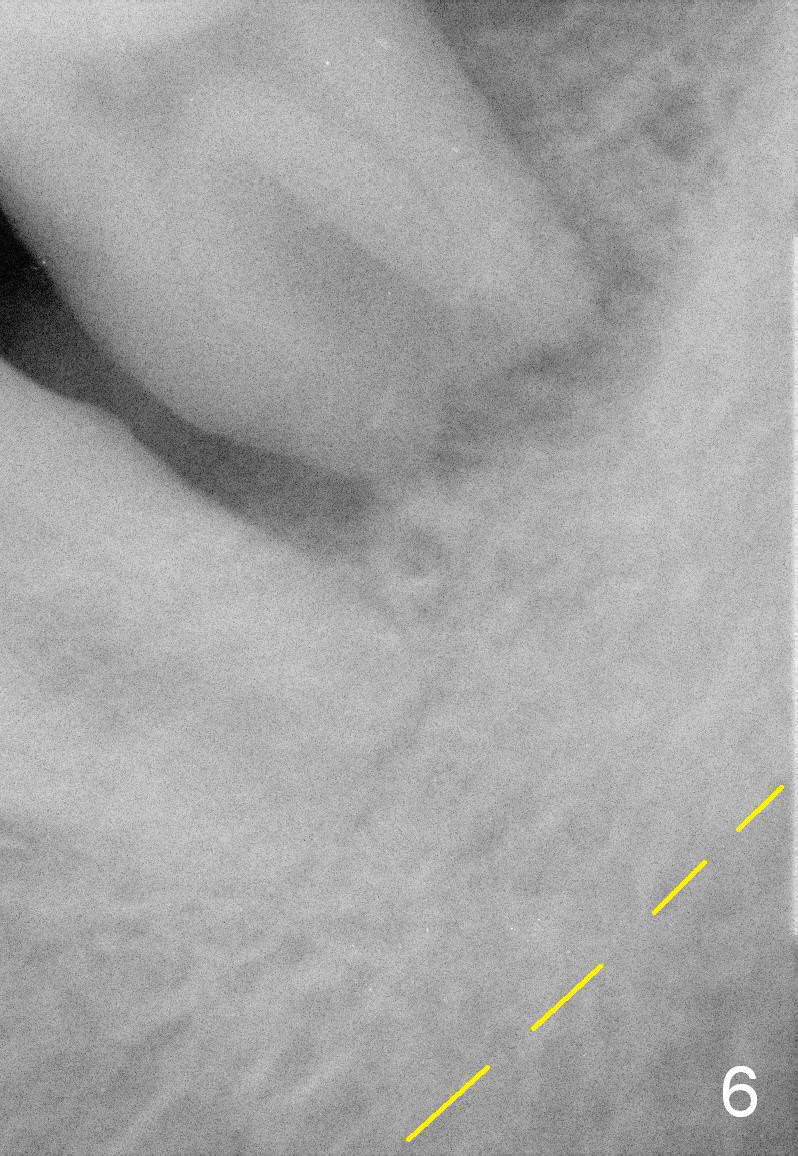

A 63-year-old man has periodontitis. The tooth #18 (probably 17) has mobility III (Fig.1). Three more PAs are taken with deeper placement of #2 sensor (Fig.2,6,7) to show the upper border of the Inferior Alveolar Canal (yellow dashed lines). The affected tooth has severe bone loss, especially mesially (Fig.2,3 (arrowheads)). No matter whether bone (Fig.4) or gingiva (Fig.5)-level implant is placed, the threads should be covered circumferentially by bone, native or grafted (red circles). In Fig.5, the threads are apical to black arrowheads, whereas the rough surface, which should be also contacted by bone, is the lower half above the black arrowheads.